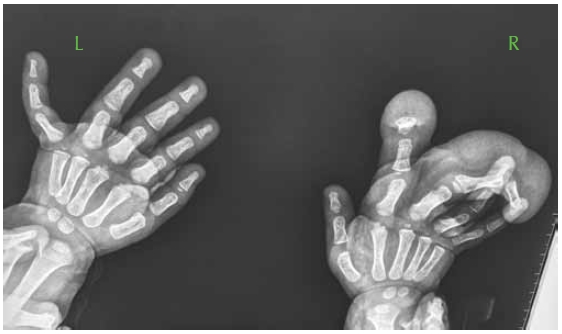

Clinical examination at the age of 17-years showed severe short stature of –3SD, her OFC was around the 50 percentile as well as her weight. No dysmorphic facial features were noted. Musculoskeletal examination showed mild ligamentous laxity of the upper limbs, though restrictions of the joints mobility were observed in her lower limbs. Her upper limbs were of normal development and her spine showed no peculiar deformities with normal trunk development. Her hands and feet were normal. Examination of the lower limbs showed very short lower segment in comparison with a normally developed upper segment. Muscular wasting was a notable feature. In her early life she was investigated for myopathy. Serum creatine kinase and plasma lactate were normal. Electromyography showed minimal changes, and past muscle magnetic resonance imagic (MRI) showed non-specific and non-diagnostic changes. Muscle biopsy and muscle respiratory chain were normal as well. No definite diagnosis has been established since the muscle biopsy and the other investigations were non-compatible with myopathy. Hormonal investigations included thyroid hormones; adrenocorticotropic hormone and growth hormone were negative as well.